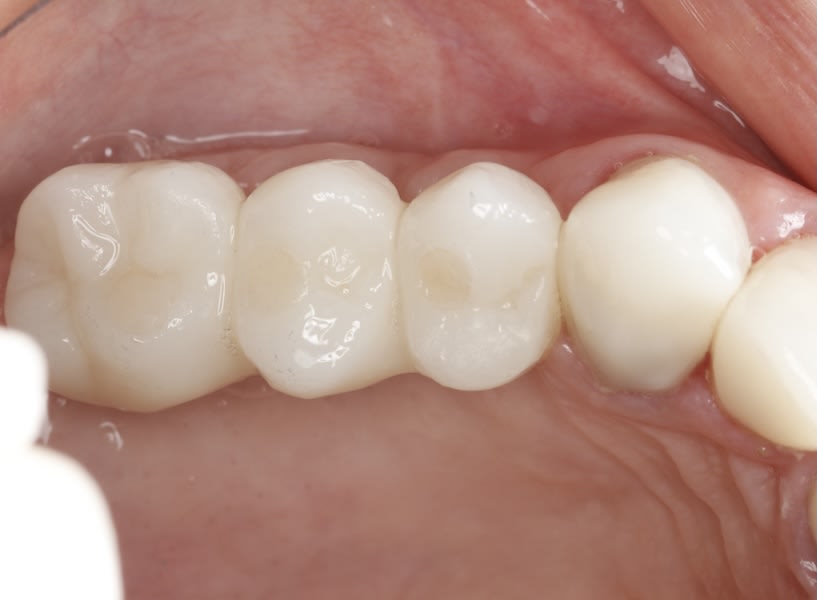

Case 1 (Figure 3 through Figure 24) depicts a 3-year follow-up of combined osseodensification sinus protocol IV in a severely resorbed maxillary ridge with ≤0.5 mm bone height in molar sites and horizontal deficiency at the first premolar site, using a two-stage approach for implant placement.